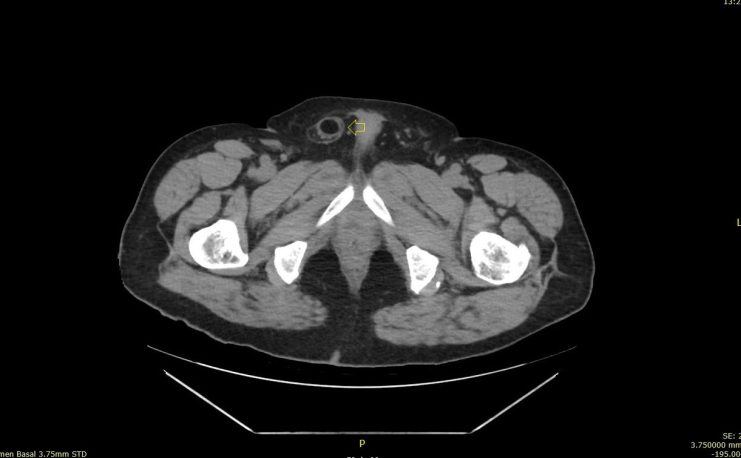

291. Lipoma de cordón y hernia inguinal.

La hernia era una hernia más, el bultoma me hizo saltar las alarmas y se lo comuniqué al radiólogo responsable. Ante la sospecha razonable de que pudiera ser un tumor, decidió ampliar con un TAC de Pelvis sin CIV que demostró la existencia tumonal benigna que correspondía con un lipoma de cordón, benigno, por su aspecto amable, bordes definidos, tabique externo y centro graso.

Hernia inguinal, con foramen de 15 mm, con introduccion en saco herniario de 3 cms, de grasa omental. Imagen nodular en cordon, distal, de 2 cms, que sugiere patologia benigna.

En una misma región coexistiendo dos figuras patológicas. Fue muy bonito ver que la hernia tocaba el lipoma y retrocedía, disfruté comprobando que los hallazgos ecográficos se confirmaron con el scanner. El caso es precioso y quería que lo vieses, y en esta noche lluviosa y fría, te lo dejo en imágenes…Espero que te guste.

La imagen 12, lo que corroboraba la sospecha de lesión tumoral en el cordón a expensas de la coexistencia de una hernia en esa localización. Precioso, TODO.